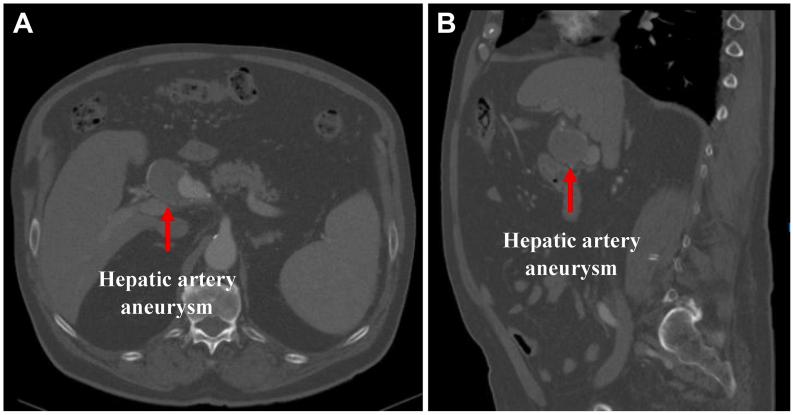

Balloon-expandable covered stenting of a large right hepatic artery aneurysm.

Leaking hepatic artery aneurysm successfully treated with covered stent.

Endovascular Treatment of Proper Hepatic Artery Aneurysm - Case Report.

Open surgical repair of giant hepatic artery aneurysm.